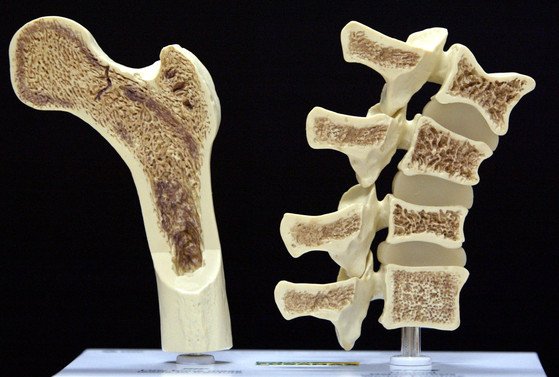

골다공증에 좋은 음식 10가지에 대해서 살펴보겠습니다. 골다공증은 뼈의 밀도가 감소되어서 쉽게 골절이 일어나는 질병이고요. 골다공증이 있다고 하면 관절 통증 및 보행에 괴로움을 느낄 수 있고요. 이러한 골다공증에 좋은 음식 10가지를 확인해 보시기 바랍니다!